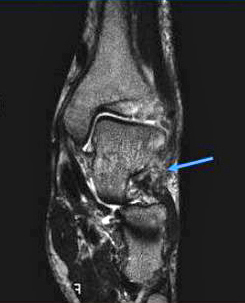

(八)跗骨窦综合征MRI检查

MRI检查适用于创伤后不明原因的持续性疼痛患者,有助于早期发现跗骨窦部位病理改变。正常跗骨窦在冠状位和矢状位MRlT1加权图像上显示高信号强度的脂肪和低信号强度的韧带组织,若跗骨窦脂肪为其他组织代替,T1、T2加权图像则均为广泛低信号强度改变,且可显示颈韧带和骨间韧带撕裂 。

跗骨窦综合征MRI表现

跗骨窦韧带撕裂,窦内结构模糊跗骨窦韧带纤维化(在T1WI和T2WI图像上呈低信号)

滑膜炎、液体和韧带扭伤(T1WI低信号;T2WI高信号)

在距下关节后面前、后微隐窝处的液性信号(T1WI低信号;T2WI高信号)

常见到踝外侧韧带撕裂,外踝肿胀